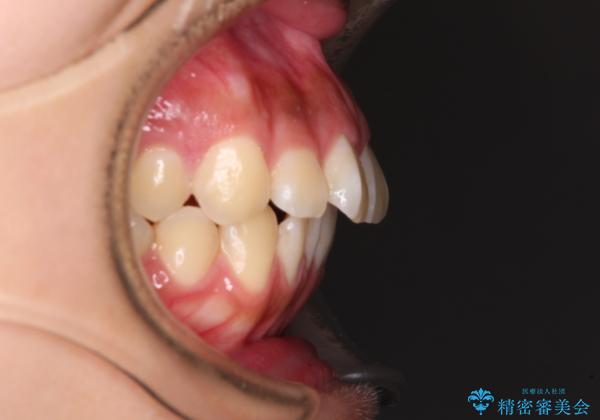

- 口元から飛び出てしまう前歯を気にして来院された患者様です。

上下前歯が嘴のように前方に突出しており、唇が閉じにくい状態であったため、上下左右の第一小臼歯4本を抜歯して、口元の突出感を改善することとしました。

目立たない装置を希望とのことで、上顎が裏側、下顎が表側のハーフリンガル装置を用いることとしました。